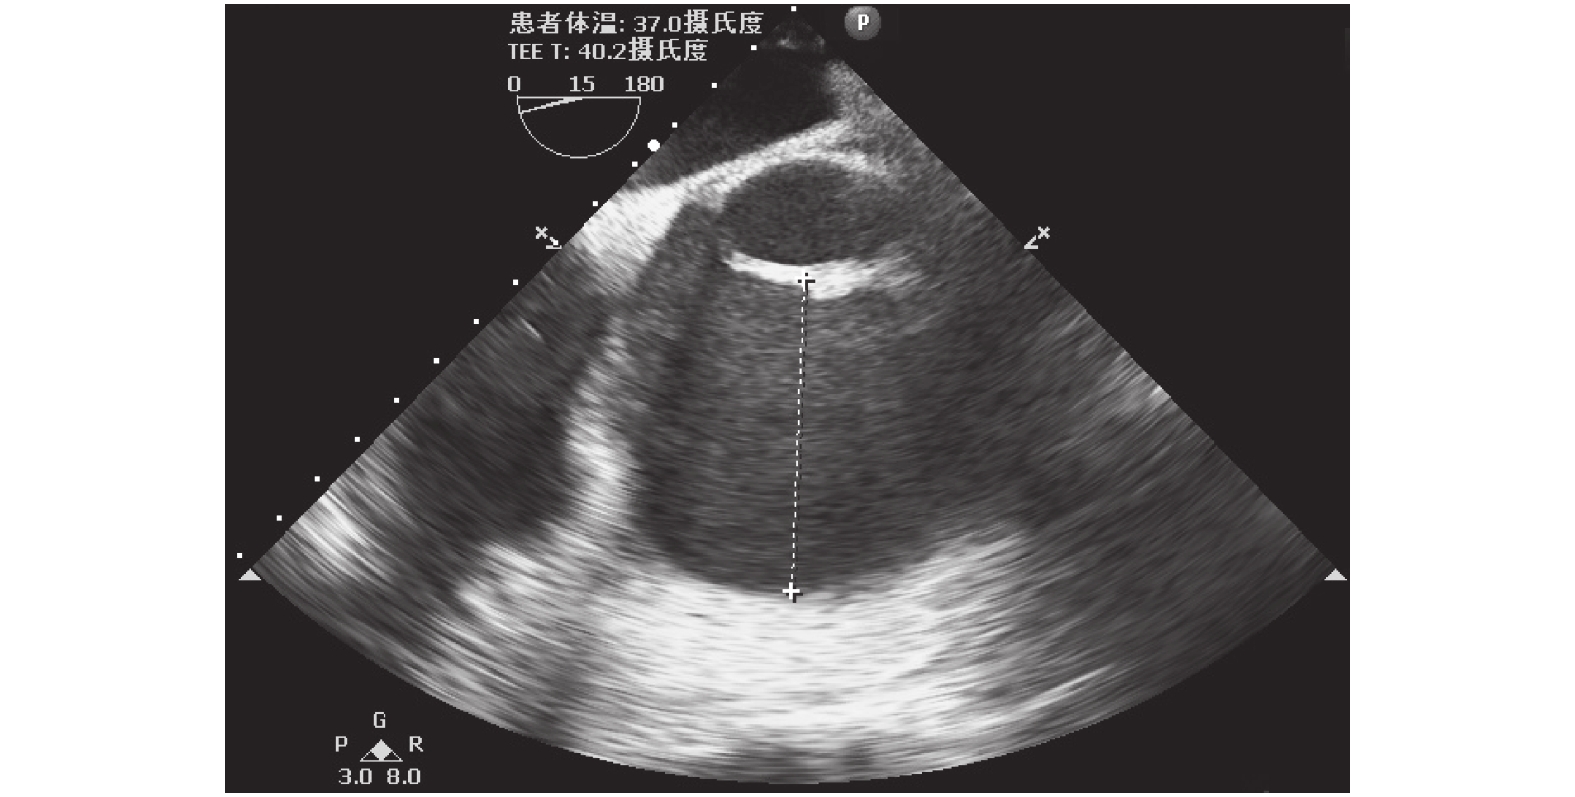

患者入手術室后進行心電監護,局部麻醉下行左側橈動脈穿刺置管連續監測動脈血壓。使用咪達唑侖 8 mg,枸櫞酸舒芬太尼 50 μg,順式阿曲庫銨 15 mg 緩慢靜脈推注誘導后插管,機械通氣潮氣量 8 ml/kg,呼吸頻率 12 次/min。右側頸內靜脈穿刺置管監測中心靜脈壓(CVP),置入經食管超聲心動圖(TEE)探頭。術中常規主動脈、上下腔靜脈插管,體外循環(CPB)轉機、降溫至 33℃,升主動脈遠段阻斷主動脈,經主動脈根部灌入含血心臟停跳液,心包內局部置入冰屑,心臟停跳。CPB 期間丙泊酚聯合瑞芬維持麻醉,平均動脈壓(MAP)45 mm Hg,加用去甲腎上腺素 0.03 μg/(min·h),維持 MAP 50 mm Hg。術中搭橋 2 根,分別為左乳內動脈-左前降支,升主動脈-大隱靜脈-第一對角支,切開右房、房間隔行二、三尖瓣成形術,復溫至體溫 36.5℃,開放升主動脈,心臟自動復跳,靜脈泵注腎上腺素 0.05 μg/(kg·h),去甲腎上腺素 0.08 μg/(kg·h),異丙腎上腺素 0.03 μg/(kg·h),米力農 0.05 mg/(kg·h),間斷推注去甲腎上腺素 20 μg,心率 110 次/min,全身動脈血壓(ABP)維持 84~70/56~46 mm Hg。動脈血氣示:pH 7.4,鉀 3.42 mmol/L,鈣 1.09 mmol/L,血糖 9.7 mmol/L,剩余堿(BE)–5.79 mmol/L。予補鉀、補鈣后,加用垂體后葉素 3 U/h,ABP 仍維持 80/48 mm Hg 左右,CVP 10 mm Hg。TEE 監測提示循環容量充足(左室舒張期末內徑 5.65 cm),心臟收縮功能良好(圖 1 、圖 2)。復查動脈血氣未見內環境紊亂。CPB 停機后患者尿量 180 ml/h,肢端溫暖。外科醫師于主動脈根部穿刺測壓 95/59 mm Hg。麻醉醫師行術中股動脈穿刺置管測壓,同時監測患者橈動脈與股動脈壓力,患者股動脈 MAP 波動于 60~70 mm Hg,較橈動脈 MAP 增高約 20 mm Hg。體外循環轉流時間 196 min,主動脈阻斷 126 min,流量 3.6 L/min。術后患者體溫 36.5℃,心率 95 次/min,股動脈血壓 103/60 mm Hg,SpO2 100.0%,靜脈持續泵注腎上腺素 0.03 μg/(kg·h),去甲腎上腺素 0.05 μg/(kg·h),順利返回心胸外科重癥監護室。術后予呼吸機輔助通氣、強心、利尿,維持內環境等對癥支持治療。患者基礎心功能差,術后第 2 d 持續應用腎上腺素 0.05 μg/(kg·h),去甲腎上腺素 0.05 μg/(kg·h),米力農 0.5 mg/(kg·h),垂體后葉素 2 U/h 維持循環。查體心率 90 次/min,血壓 110/63 mm Hg,SpO2 100.0%,四肢溫暖,雙肺呼吸音清,小便量正常,心包縱隔引流管通暢,引流量不多。患者術后第4 d 小便量明顯減少,肌酐升高,查體心率 103 次/min,股動脈 102/59 mm Hg,SpO2 99%,持續泵注腎上腺素 0.03 μg/(kg·h),米力農 0.2 m/(kg·h) 強心治療。術后第 6 d 查體心率 89 次/ min,血壓 112/65 mm Hg,SpO2 99%,停用所有血管活性藥物,局部麻醉下行纖維支氣管鏡檢查后順利拔除氣管導管。

圖1

停機后左室舒張期末 TEE 圖

圖2

停機后左室 TEE 二維圖